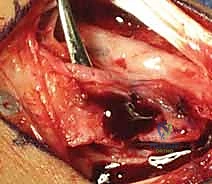

3. تحديد الشريان المغذي (The 1,2 ICSRA)

باستخدام النظارات المكبرة الجراحية (Loupes) أو الميكروسكوب الجراحي، يقوم الدكتور هطيف بالبحث عن الشريان الدقيق (1,2 ICSRA) الذي يمر بين الحيز الأول والثاني للأوتار الباسطة. يتم عزل هذا الشريان مع شريط صغير من الأنسجة المحيطة به لحمايته وضمان استمرار تدفق الدم فيه.

4. استخراج الطعم العظمي الوعائي (Harvesting the Graft)

بمجرد تأمين الشريان، يتم استخدام منشار عظمي دقيق جداً لقطع كتلة عظمية صغيرة من ظهر عظم الكعبرة، بحيث يظل الشريان متصلاً بها بإحكام. الآن أصبح لدى الجراح قطعة عظمية "حية" وجاهزة للنقل.